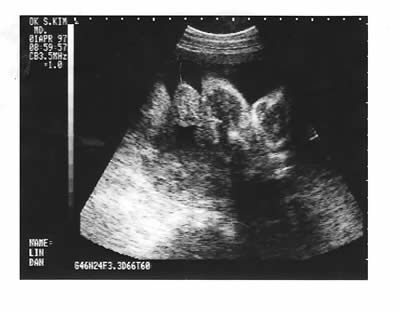

B超照片(1996年10月24日和1997年4月1日)。拜现代技术之赐,人在母腹中就可以留影。虽然影像看起来不甚清楚,医生却能告诉你这是一个健康的男孩。想当初那种喜悦之情,真是难以言表。